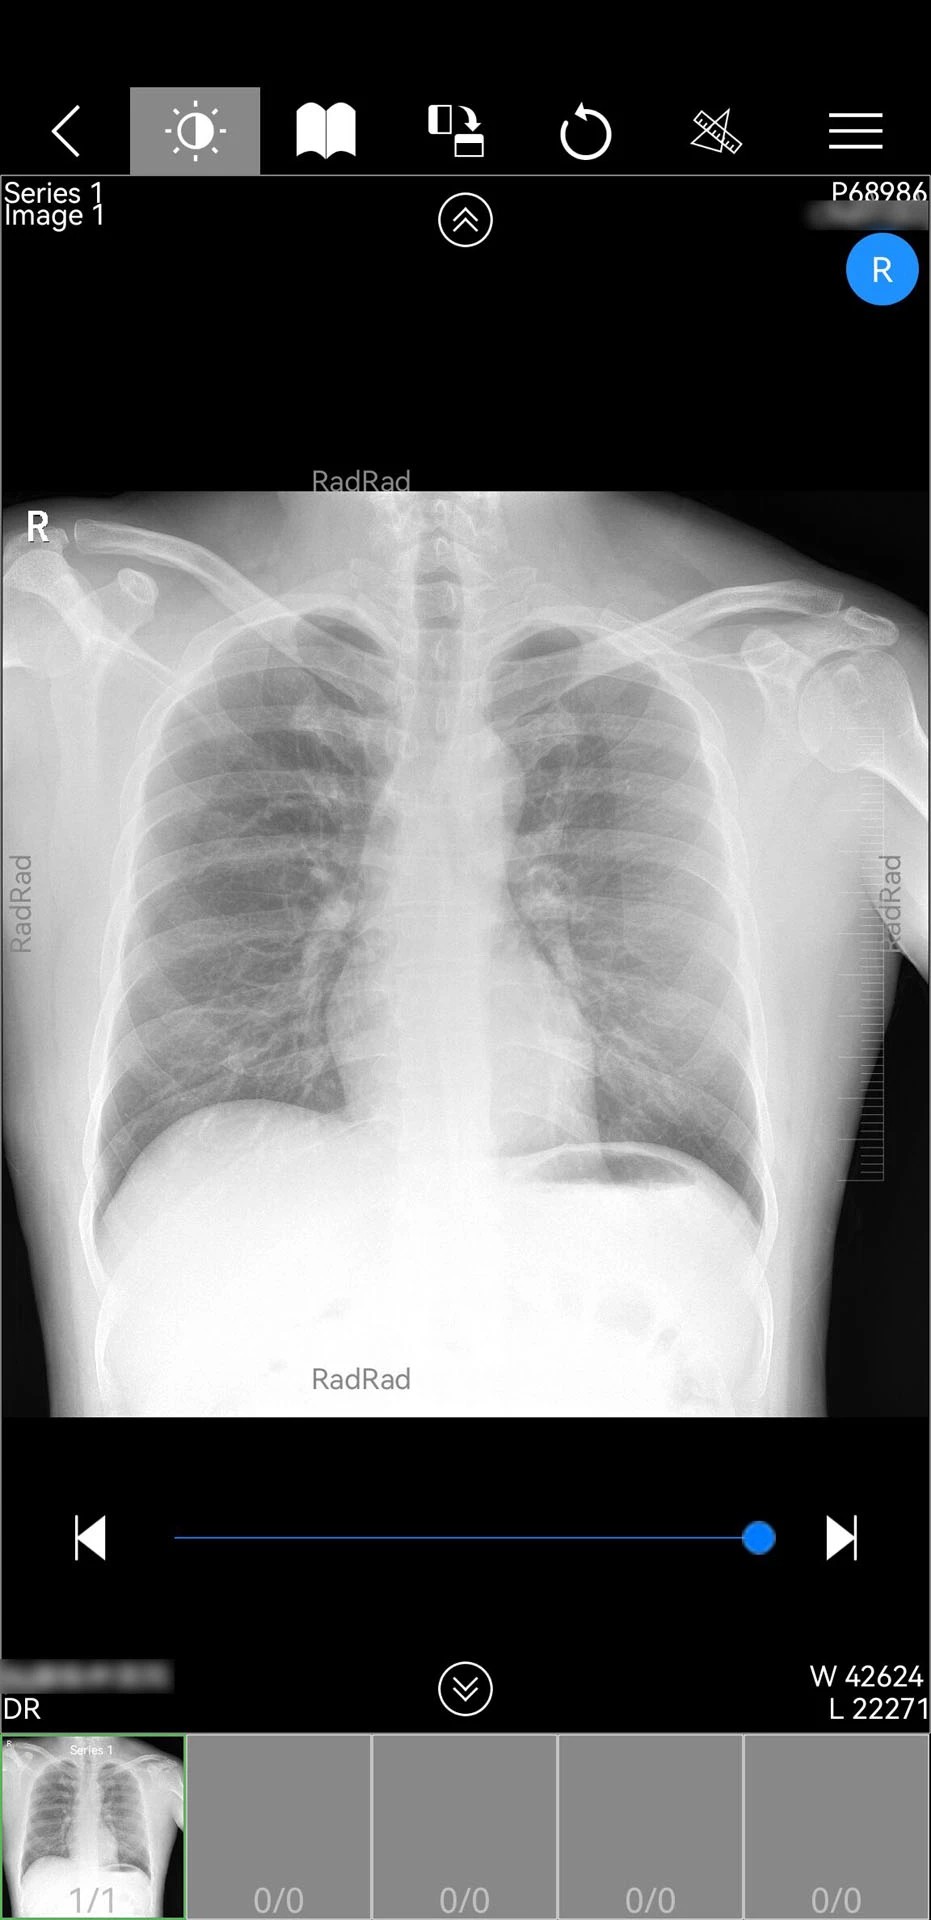

3. 影像诊断:点击“影像中心”调取患者检查数据,支持缩放、旋转、窗宽调整等操作,并可调用AI辅助诊断工具(如肺结节智能标注)生成分析报告。

1. 全场景影像支持:兼容DICOM 3.0标准,可处理CT、MRI、DSA等多模态影像,并支持三维重建、血管分析等高级后处理功能。

2. AI深度赋能:内置自然语言处理(NLP)引擎,可自动解析电子病历中的关键信息;通过深度学习模型实现肺结节、骨折等疾病的智能筛查,准确率达92%以上。